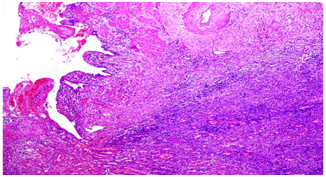

Gross pathologic examination of GB revealed 5.5 cm long, 6.0 cm maximum diameter tissue. No lymph node. The serosa of the GB was tan-brown, smooth and shiny. The hepatic surface was also tan-brown. The GB wall ranged from 0.8-1.0 cm in thickness and was grossly unremarkable. The mucosa was green and velvety, without polyps or other lesions. Microscopic examination revealed GB mucosa with focal ulceration. Lamina propria showed acute and chronic inflammatory cell infiltrate comprised of neutrophils, lymphocytes, and plasma cells. There were sheets of foamy histiocytes and few hemosiderin-laden macrophages but no evidence of granuloma or malignancy (Figure 2).

Figure 2 Microscopic examination revealed GB mucosa with focal ulceration. Lamina propria showed acute and chronic inflammatory cell infiltrate comprised of neutrophils, lymphocytes, and plasma cells. There were sheets of foamy histiocytes and few hemosiderin-laden macrophages but no evidence of granuloma or malignancy.

Title: Low power view of xanthogranulomatous gallbladder (H&E stain).